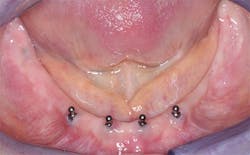

Overdenture supported by four to six small-diameter implants (SDIs) (Figures 3–4)

In 1997, the FDA cleared small-diameter implants, less than 3 mm in diameter, for long-term use, and millions have been served successfully since. Early forms of small-diameter implants were made from commercially pure titanium, which did not have adequate strength or rigidity for long-term use. However, currently SDIs are made from titanium alloy, which is much stronger and rigid. Often, edentulous patients do not have enough bone to allow placement of conventional-diameter implants in the canine areas. The minimal amount of bone for conventional-diameter implants - 4+ mm in diameter and ~12 mm in length without grafting bone - requires at least 6 mm of bone in a facial-lingual dimension and at least 13 mm or 14 mm of bone in a crestal-apical location. If adequate bone is available in the premolar or molar areas, more stability and retention can be obtained by placing additional implants in those locations.

Small-diameter implants can be placed in bone as minimal as 3 mm to 4 mm from facial to lingual, since the screw form of the SDI spreads the bone.13-16 When adequate bone is not present for placement of conventional-diameter implants in the mandible, SDIs spaced equally from canine to canine are a logical choice.

The following technique is suggested when retaining the previously made or new denture with four SDIs on the mandible:

• Diagnosis, treatment plan, and patient acceptance of four SDIs and a reline or rebase of a previously made denture or fabrication of a new denture.

• Placement of the four SDIs (1.8 mm to 2.9 mm in diameter) in the mandibular arch spaced primarily from canine to canine. Since maxillary anterior bone is not as dense as mandibular anterior bone, most dentists are placing six SDIs from canine to canine in the maxillary arch. As stated previously, the farther distal the implants can be placed, the better the denture stability and retention.

• Deciding on whether or not to load the implants immediately after placing them or waiting is different from the description above for conventional-diameter implants. Most SDIs placed under complete dentures do not require a flap and are minimally invasive.16 If the implants are stable in bone when placed, most dentists load them immediately with success.

• Attaching the implants to an acceptable previously made denture, a previously made denture to be rebased, or to a new denture is the same as described in the above narrative for conventional-diameter implants.